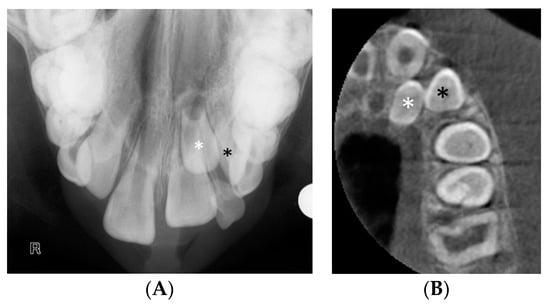

The presence of supernumerary teeth can pose a challenge to the clinician’s ability to distinguish the supernumerary from the true tooth, as illustrated in Figure 4. This case was referred for CBCT to differentiate the true lateral incisor tooth and the supplemental tooth. The supplemental lateral incisor was identified as the palatally positioned tooth, following a CBCT assessment of the more rudimentary tooth morphology. Precise morphological measurements and accurate localisation of teeth from CBCT images allow the clinician to make an informed decision on which tooth to extract and the optimal surgical approach to reduce the risk of damage to the true tooth.

Figure 4.

(A) The upper standard occlusal shows a supplemental tooth in the maxillary left lateral incisor area. It is difficult to discern from the conventional views which of the two teeth, marked with a white and a black asterisk would be morphologically optimal to serve as the lateral incisor. (B) CBCT axial view of the left maxilla. An analysis of the dimensions of the teeth revealed that the tooth marked with the white asterisk was smaller compared to the adjacent unerupted tooth and the contralateral lateral incisor, and as such, more likely to represent the supplemental lateral incisor.